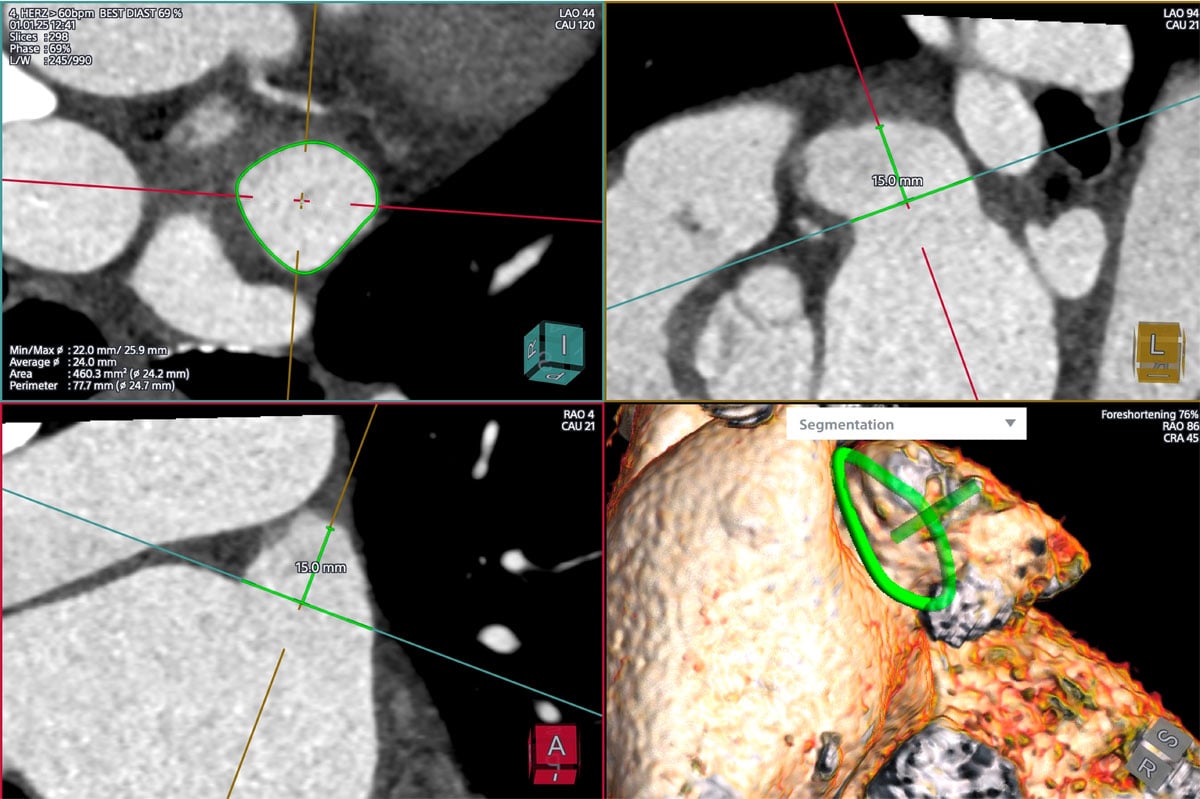

LAA closure - CT reconstruction

Min/max diameter: 22.0/25.9mm

Average diameter: 24.0mm

Area: 460mm2 (average 24.2mm)

Perimeter: 77.7mm (average 24.7mm)

Depth: 15mm

Diagnostic workup: cardiac CT reconstruction

- Cardiac CT allowed for reconstruction by FEops software modelling

Given the elevated thromboembolic risk with paroxysmal atrial fibrillation and GI bleeding under DOAC, the decision was made to plan a left atrial appendage occlusion followed by dual antiplatelet therapy for 3 months. A CT and a TOE was performed in this case for planning the procedure, as CT revealed a challenging morphology for both single- and double-disc devices with a shallow LAA (15mm depth) and an inferior-bend chicken wing morphology.